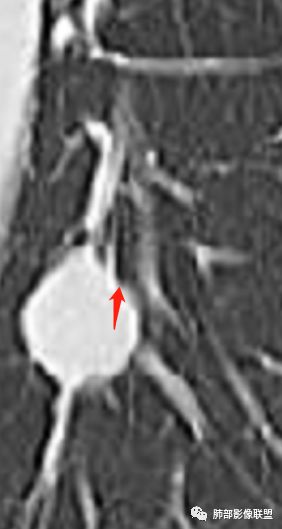

M-Imaging :周围有黑边,错构呢?南边:如果明确没堵塞就好办这个最主要的就是这个支气管是否堵塞没堵塞,支持PSP杨泽锋:如果是气管腔内起源的那就要考虑类癌M-Imaging :不见明显冰山征,没有钙化南边:心里不是很踏实,就是没看到支气管全景Forever:强化如果不高 我还是考虑小细胞肺癌或者腺癌

崔刚:有个层面支气管在病灶周边Yiren  Sishui(厶水伊人):其实就是PSP与类癌的鉴别M-Imaging :Forever:如果分不清结构关系了 这个时候强化还是有很大参考价值M-Imaging :周围有黑边崔刚:没有钙化和脂肪,张老师是不是考虑错构瘤?徐超:黑边是想说错构瘤M-Imaging :是啊滴水海:psp也可Forever:不像 觉得ct值有点高。一般错构瘤ct值低于20,没有钙化

滴水海:有黑晕更支持pspM-Imaging :黑边代表局限肺气肿错构瘤,应该和血管没有关系,这例血管贴近毛勤香:考虑PSP或错构瘤,类癌代排南边:我的判断原则:支气管无关——良性、间叶来源良性,强化明显——PSP,尤为明显——糖瘤,不明显——错构瘤

wonderful:纵膈有吗徐超:隆突下没有肿大淋巴结。思路没问题,主要还是支气管的关系。还有CT值,有测量值最好。强化不同疾病范围不同,虽然有叠加Coke with ice:这个病灶好像有浅分叶,是否有鉴别意义呢南边:可能绕过去了。浅分叶没什么价值,深分叶有Forever:动脉期强化不太均匀 而且ct值不高我觉得有提示意义

M-Imaging :PSP强化应该达到一百多吧

徐超:不一定,看psp处于那个期,如果硬化期或纤维化期,强化就不一定高。

强化特别高的,一般处于血管瘤样区为主

M-Imaging :对,PSP不强化的,会有钙化,营养不良性钙化,小的PSP,强化还是很明显的